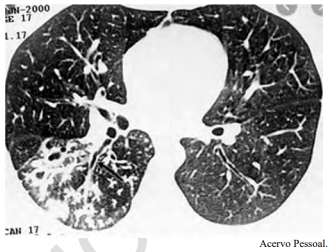

Um adolescente de 17 anos de idade procura atendimento em função de tosse vespertina, febre e hemoptise em pequena quantidade. Refere sudorese noturna e perda de peso. A tomografia de tórax apresenta nódulos centrolobulares com padrão de árvore em brotamento, além de pequenas cavitações espessas e de paredes irregulares, bem como brônquios espessados em segmento posterior do lobo inferior direito, conforme a imagem a seguir.

Tendo em vista esse caso clínico, a imagem apresentada e os conhecimentos médicos correlatos, julgue o item a seguir.